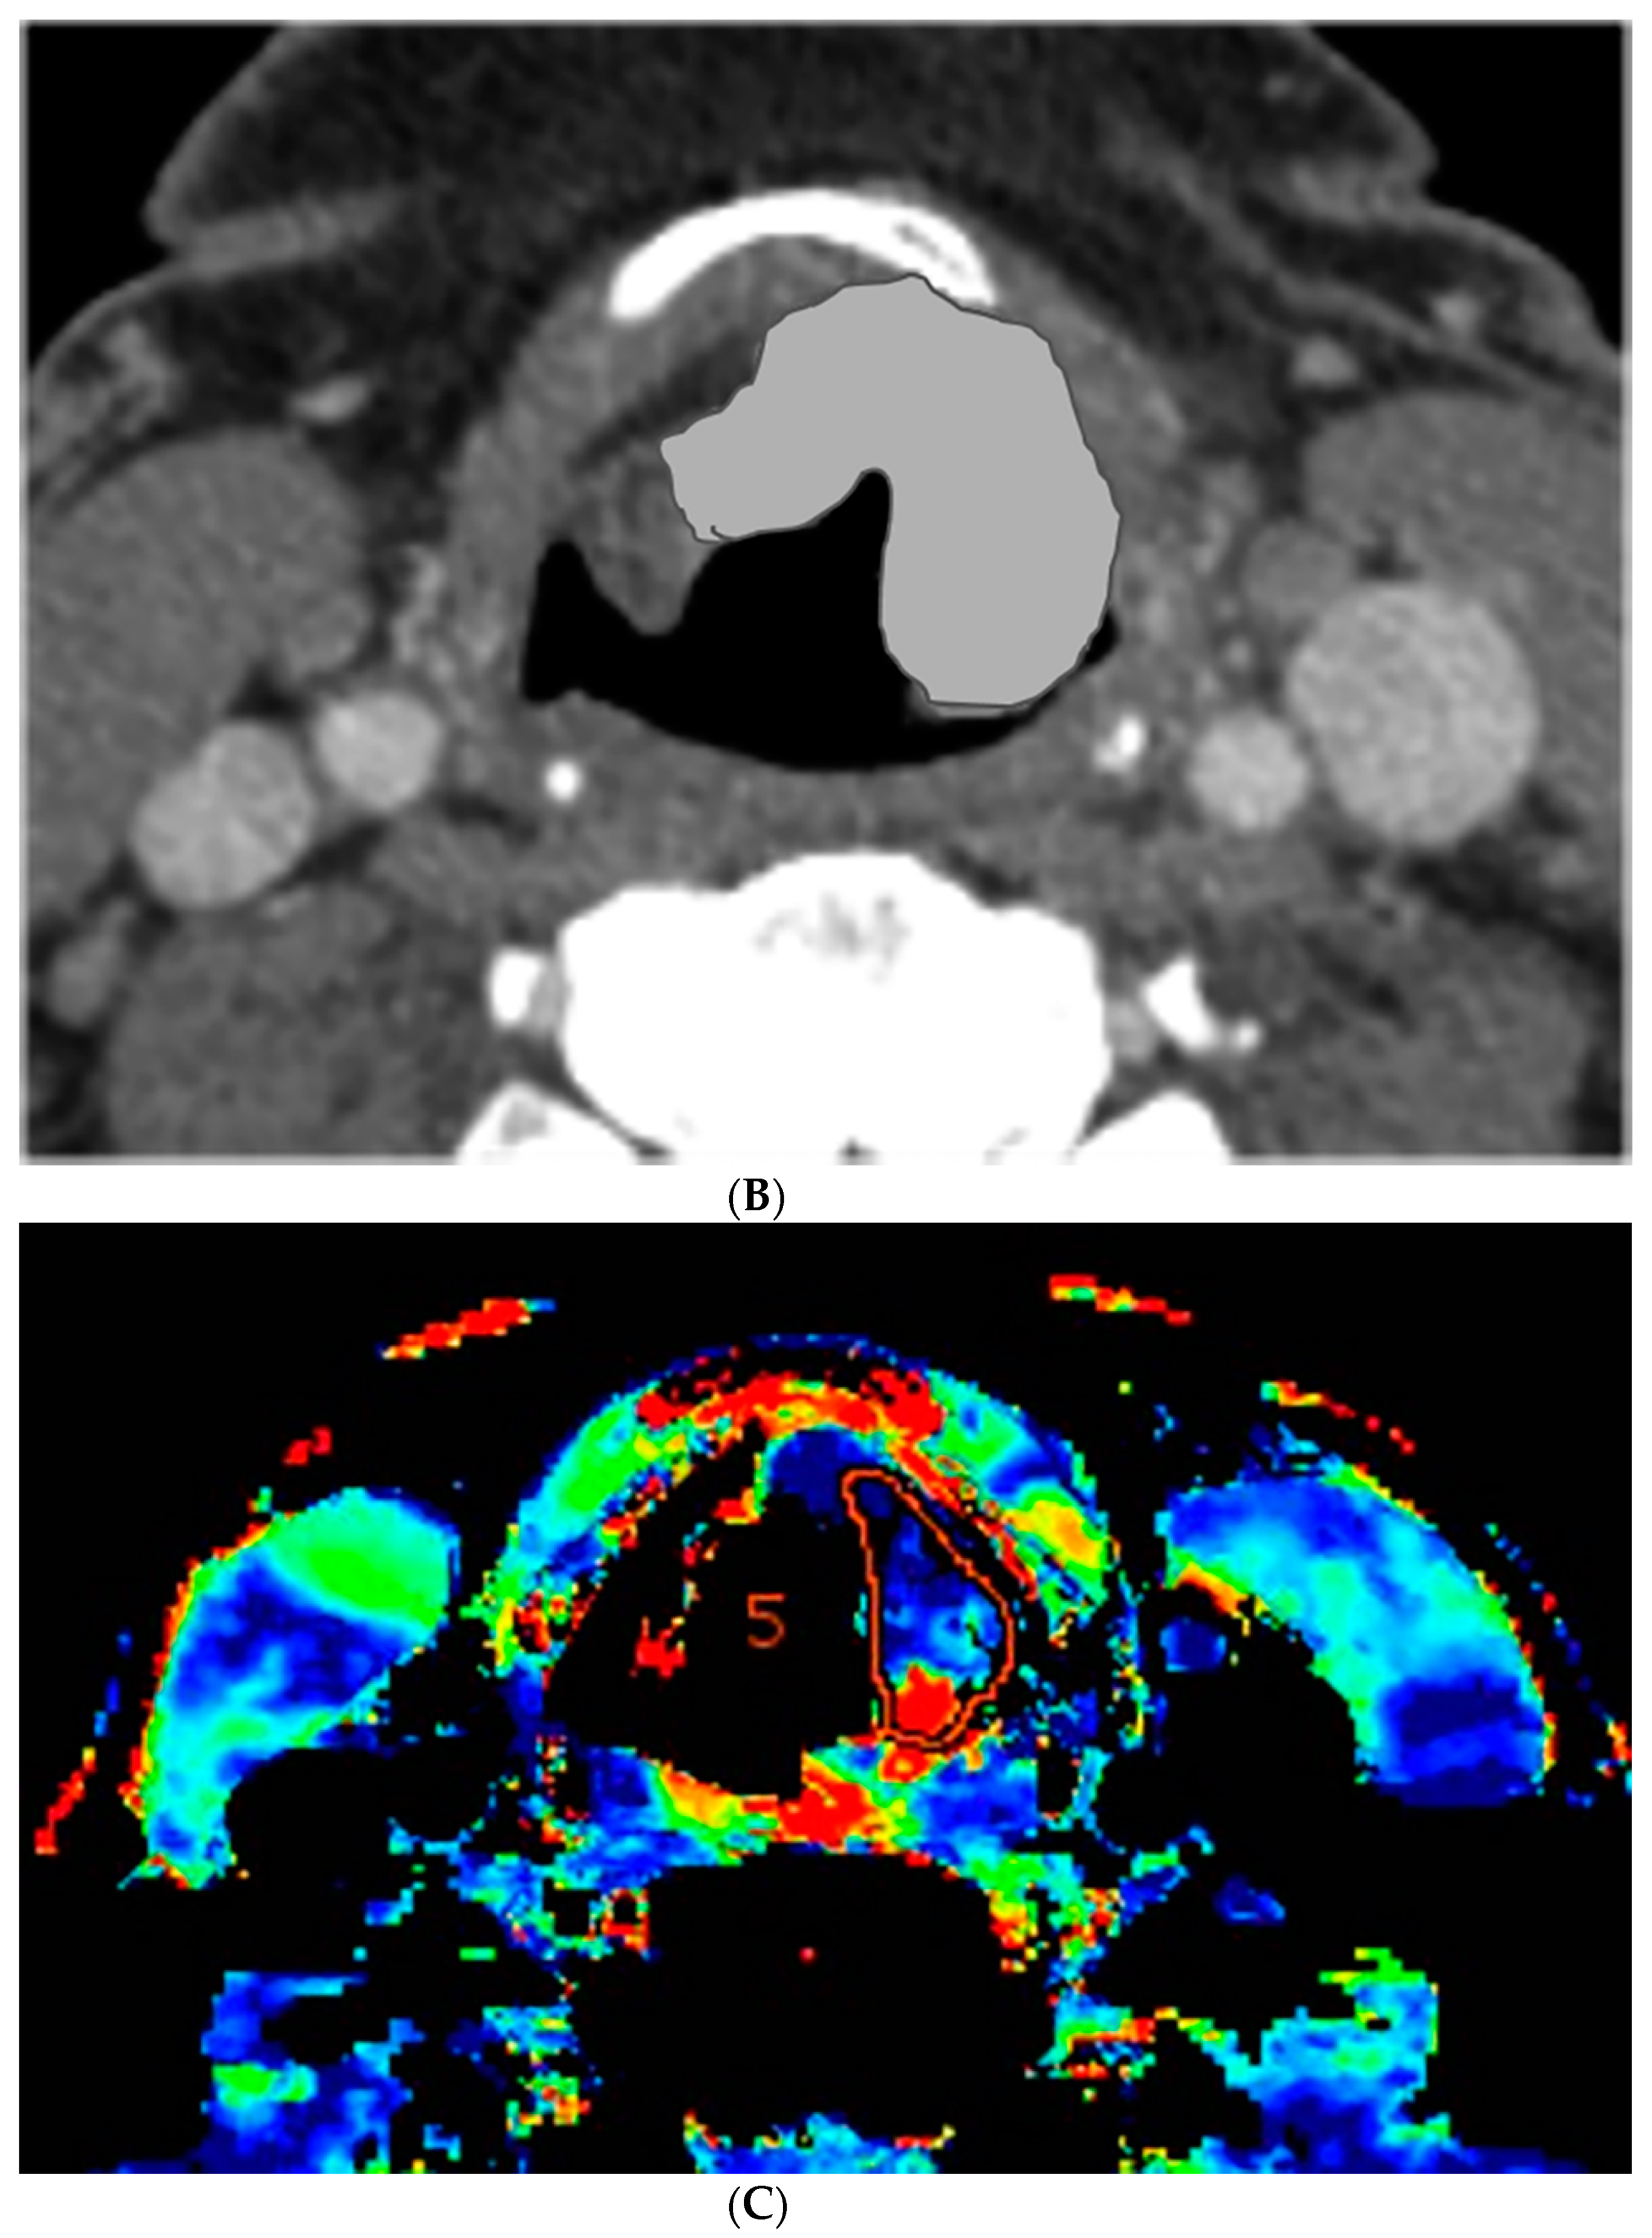

Figure 2.

CT and perfusion sections of laryngeal carcinoma on post-treatment images. Axial sections show the grayscale image (A) and outlines for the following: computer (B) and perfusion (C).

The percent volume change ICC of the computer with Radiologist 1 or Radiologist 2 were 0.80 and 0.74, respectively. The percent volume change ICC between the two radiologists was 0.73. The differences in the computer-versus-radiologist and radiologist-versus-radiologist ICCs did not achieve statistical significance. Examples of the semi-autonomous computerized 3D level-set segmentation are demonstrated in Figure 1 and Figure 2.